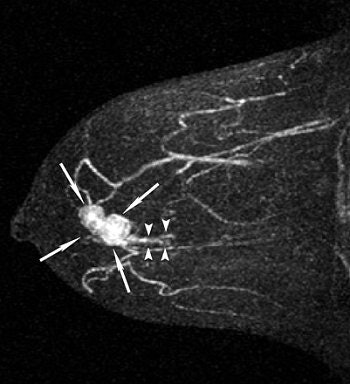

The overall survival rate for women who undergo breast-conserving surgery is significantly lower when surgical margins are positive for tumor cells than with negative margins, and a positive surgical margin is generally the result of inadequate resection of the cancer's intraductal component, explained Dr. Akiko Shimauchi and colleagues from the Tohoku University Graduate School of Medicine in Sendai, Japan. Accurate preoperative diagnosis of the intraductal component is necessary to achieve a cancer-free surgical margin. Previous studies have evaluated MDCT and MRI in this setting, but these were done before current advances in CT technology, and often used two different patient populations.

"We compared the accuracy of MDCT and MRI for evaluating intraductal components of breast cancer in the same population," wrote Shimauchi, who is now at the University of Chicago in Illinois. "We propose that MRI is better than MDCT for evaluating tumors with ductal extension, especially those with relatively small intraductal components" (AJR, August 2006, Vol. 187:2, pp. 322-329).

This study included 69 patients who were diagnosed with breast cancer between 2000 and 2004, and who underwent breast-conserving surgery, as well as preoperative MDCT and MRI. CT exams were done with a collimation of 1.25 mm and a pitch of 6 (LightSpeed QX/i, GE Healthcare, Chalfont St. Giles, U.K). MR imaging was performed on a 1.5-tesla unit (Magnetom Vision, Siemens Medical Solutions, Malvern, PA). Patients were scanned in the prone position and the protocol included bilateral fat-saturated T1-weighted imaging and T2-weighted imaging. Dynamic contrast-enhanced studies in the sagittal plane were also done.

| A 43-year-old woman with invasive ductal carcinoma in right breast. Above, maximum intensity projection (MIP) image of MDCT images reveals location of main tumor (arrows) but not intraductal component. Below, MIP image of MRI reveals a clumped enhancement (arrowheads) distal to main tumor (arrows), which was suspected to be intraductal component. Intraductal component distal to main tumor was confirmed on histopathologic examination. Shimauchi A, Yamada T, Sato A, Takase K, Usami S, Ishida T, Moriya T, and Takahashi S, "Comparison of MDCT and MRI for Evaluating the Intraductal Component of Breast Cancer" (AJR 2006; 187:322-329). |

Based on histopathology results, the majority of the tumors (63) were invasive ductal carcinoma and 44 of these had an intraductal component. Two radiologists reviewed the images in consensus, taking into consideration the distribution pattern of lesion enhancement and the morphologic typing of invasive tumors.

All 69 cases of invasive carcinoma were depicted on MDCT and MR images. The sensitivity of CT for detecting an intraductal component was 61%. Its specificity was 88% and the accuracy was 71%. In comparison, MR's sensitivity came in at 75%, its specificity at 88%, and its accuracy at 80%. In six patients, intraductal components were seen on MRI but not on CT. Both modalities missed intraductal components in 11 cases.

"There were no cases in which MDCT revealed an intraductal component that was undetectable with MRI," the authors stated. "The greater contrast obtained with MRI by using the subtraction technique probably contributed to the higher sensitivity of this method."

In terms of the morphologic typing of tumors, both modalities generally underestimated the length of the intraductal component. The correlation co-efficient between the length of the main tumor on MDCT and histopathology was 0.72 versus 0.70 for MRI. However, "underestimation of the length of the intraductal component by 15 mm or more was significantly less frequent with MRI than with MDCT," the group wrote.